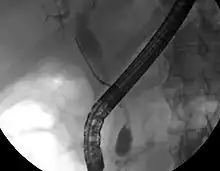

While abdominal imaging can be useful in the diagnosis of cholangiocarcinoma, direct imaging of the bile ducts is often necessary. Endoscopic retrograde cholangiopancreatography (ERCP), an endoscopic procedure performed by a gastroenterologist or specially trained surgeon, has been widely used for this purpose. Although ERCP is an invasive procedure with attendant risks, its advantages include the ability to obtain biopsies and to place stents or perform other interventions to relieve biliary obstruction.[12] Endoscopic ultrasound can also be performed at the time of ERCP and may increase the accuracy of the biopsy and yield information on lymph node invasion and operability.[55] As an alternative to ERCP, percutaneous transhepatic cholangiography (PTC) may be utilized. Magnetic resonance cholangiopancreatography (MRCP) is a non-invasive alternative to ERCP.[56][57][58] Some authors have suggested that MRCP should supplant ERCP in the diagnosis of biliary cancers, as it may more accurately define the tumor and avoids the risks of ERCP.[59][60][61]